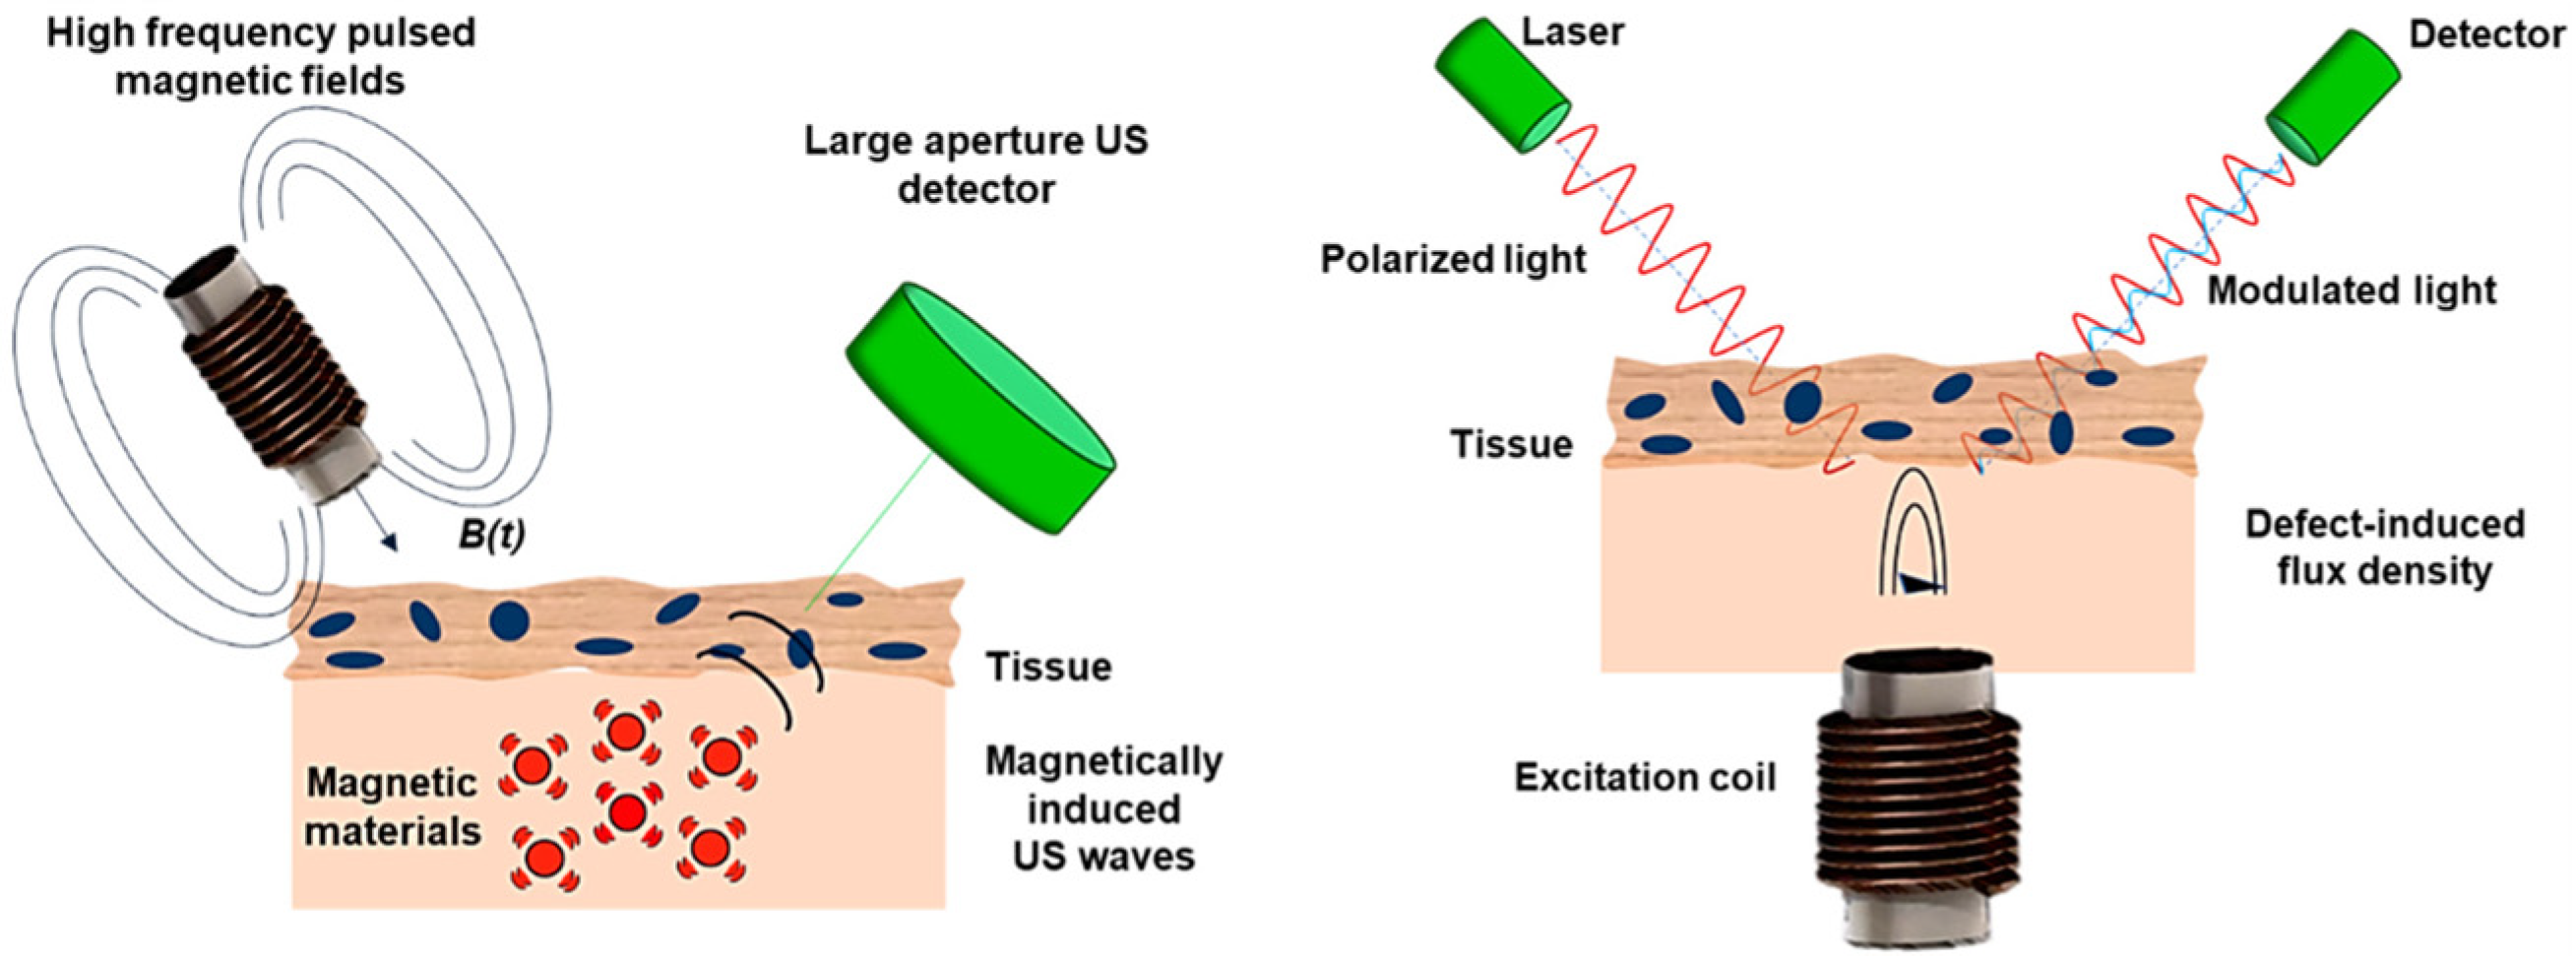

2.5.2. Magnetomotive Assisted Imaging

- Mehrmohammadi, M.; Oh, J.; Ma, L. Imaging of iron oxide nanoparticles using magneto-motive ultrasound. In Proceedings of the 2007 IEEE Ultrasonics Symposium Proceedings, New York, NY, USA, 28–31 October 2007; pp. 652–656. [Google Scholar] [CrossRef]

- Evertsson, M.; Ramalli, A.; Pavan, T.Z. Towards real-time magnetomotive ultrasound imaging. In Proceedings of the 2017 IEEE International Ultrasonics Symposium (IUS), Washington, DC, USA, 6–9 September 2017. [Google Scholar] [CrossRef]

- Evertsson, M.; Cinthio, M.; Fredriksson, S.; Olsson, F.; Persson, H.; Jansson, T. Frequency-and phase-sensitive magnetomotive ultrasound imaging of superparamagnetic iron oxide nanoparticles. IEEE Trans. Ultrason. Ferroelectr. Freq. Control. 2013, 60, 481–491. [Google Scholar] [CrossRef]

- Evertsson, M.; Cinthio, M.; Kjellman, P. In vivo magnetomotive ultrasound imaging of rat lymph nodes—A pilot study. In Proceedings of the 2015 IEEE International Ultrasonics Symposium, Taipei, Taiwan, China, 21–24 October 2015. [Google Scholar] [CrossRef]

- Oh, J.; Feldman, M.D.; Kim, J.; Condit, C.; Emelianov, S.; Milner, T.E. Detection of magnetic nanoparticles in tissue using magneto-motive ultrasound. Nanotechnology 2006, 17, 4183–4190. [Google Scholar] [CrossRef]

- Mehrmohammadi, M.; Shin, T.-H.; Qu, M.; Kruizinga, P.; Truby, R.L.; Lee, J.-H.; Cheon, J.; Emelianov, S.Y. In vivo pulsed magneto-motive ultrasound imaging using high-performance magnetoactive contrast nanoagents. Nanoscale 2013, 5, 11179–11186. [Google Scholar] [CrossRef] [PubMed]